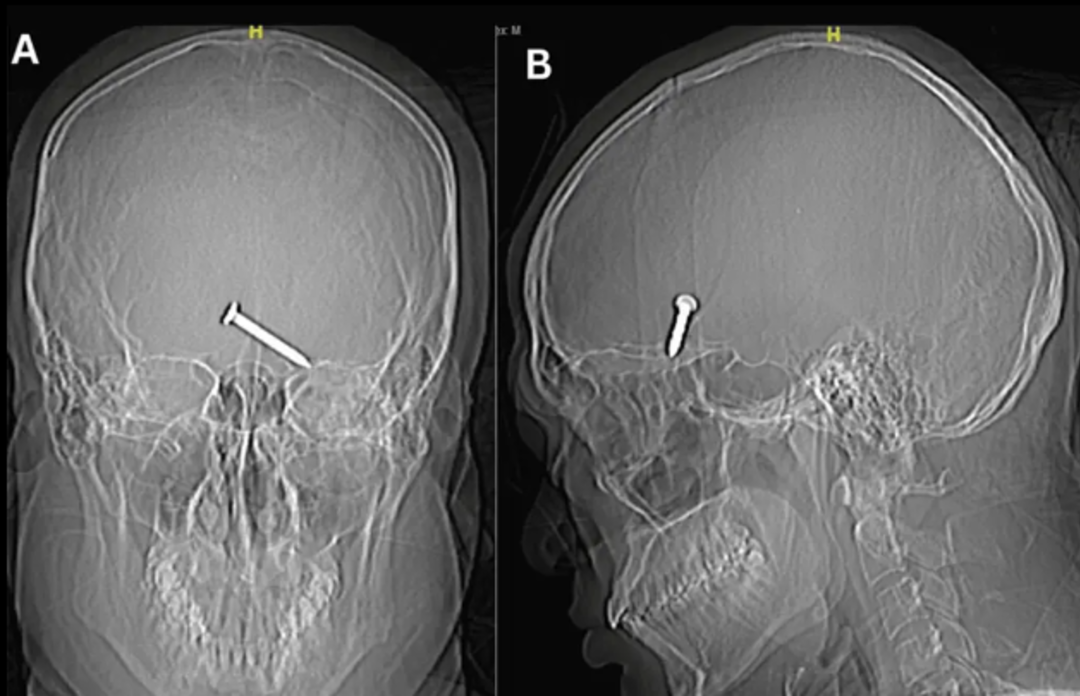

Röntgen görüntüleri, 3,2 cm büyüklüğündeki çivinin, hareket ve konuşma için hayati önem taşıyan beyninin ön lobunun derinliklerine saplandığını gösterdi.